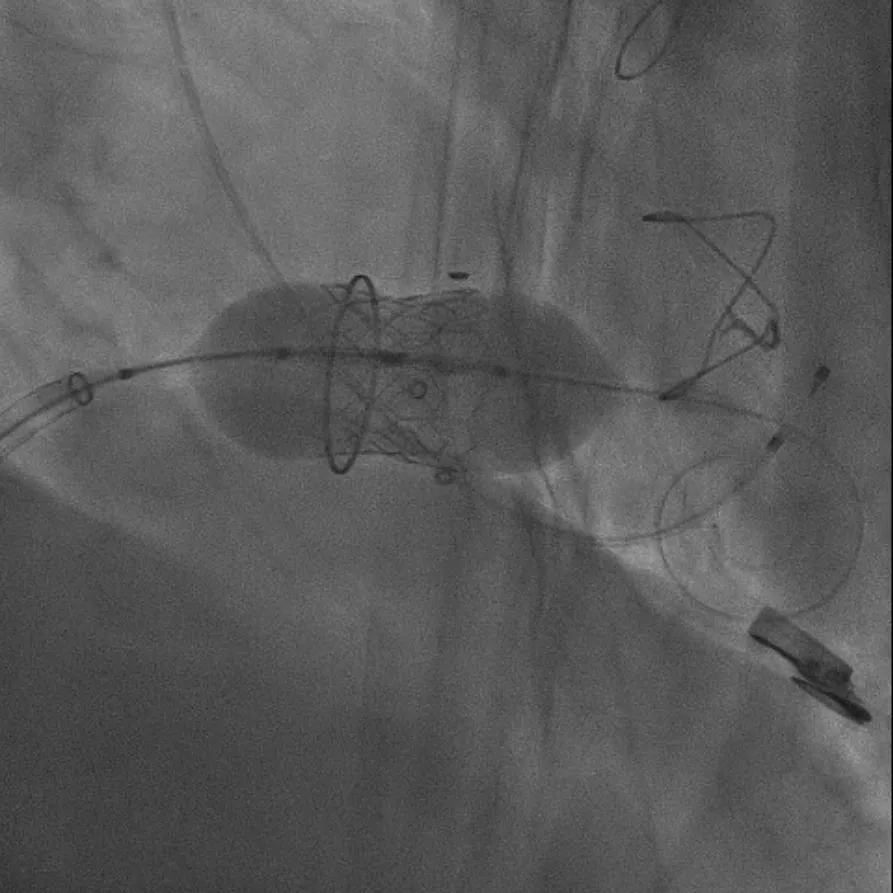

▲瓣膜释放瞬间